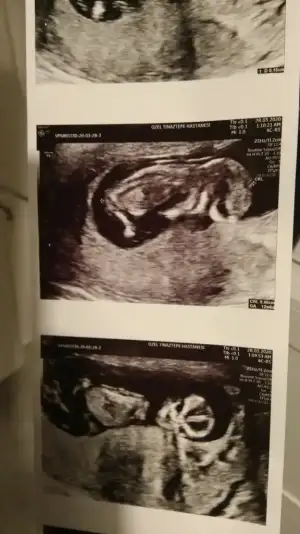

Erkek gibiBuda diğer pozu o gün ki ölçüm olmayan ters duruyordu bunda ondan çevirip çektim resmini bunda da belli olmazsa 12 gün sonra kontrolümüz var o zaman atarım 14 haftalık olacak kısmetse o zaman ❤Ikra meyra cvp için teşekkür ederim ❤ diğer konuya da 6 haftalık halini atmıştım ama görmemiş tiniz sizin tahminleriniz genel olarak tutuyor ❤

Evet inşallah yaşayan ilk olcakErkek gibiteşekkur ederim evet cogunluk tutuyor bazı usg lerde yanıltıyor bazen pozisyonları nubu değiştiriyor vs ilk bebekmi

Teşekkür ederim ben sizin sandım herkes siiz etiketleyinceRc ederim diger taraf benim konum degil ama orası aktifde değil arada etiket yapanlar var onlara cvp veriyorumbuna göre kız ama tutmayabilir kese konumu en iyi nub 11 12 13 haftalar olmalı

Sizinki kıza benziyorHer iki doktor farkli soyledi cinsiyetini 10ngun sonra kesin soyleriz dedi son fotograflar yeni bacak arasi net dikattli bakinca belki fikrin netlesir belki canim![]()

Sizinki de erkek bebek gibi14 haftalık tahmin edermisiniz

kıza benzettimMerhabalar bizde burda 11 haftadaydik bizede tahmin edebilirmisiniz rica etsem ❤

Teşekkür ederim önce sağlık tabiki ama gönlüm den de kız geçiyorkıza benzettim